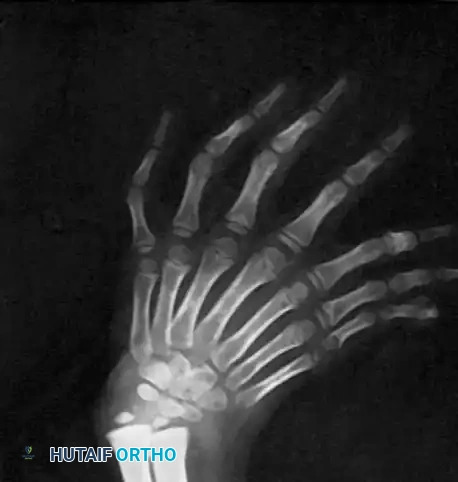

RADIOGRAPHIC EVALUATION

Standard orthogonal radiographs of the entire upper extremity are mandatory. Imaging will reveal the absence of the radius and the presence of two ulnas. The carpus is widened, often with duplicated triquetrum, hamate, and pisiform bones, while the scaphoid and trapezium are absent.